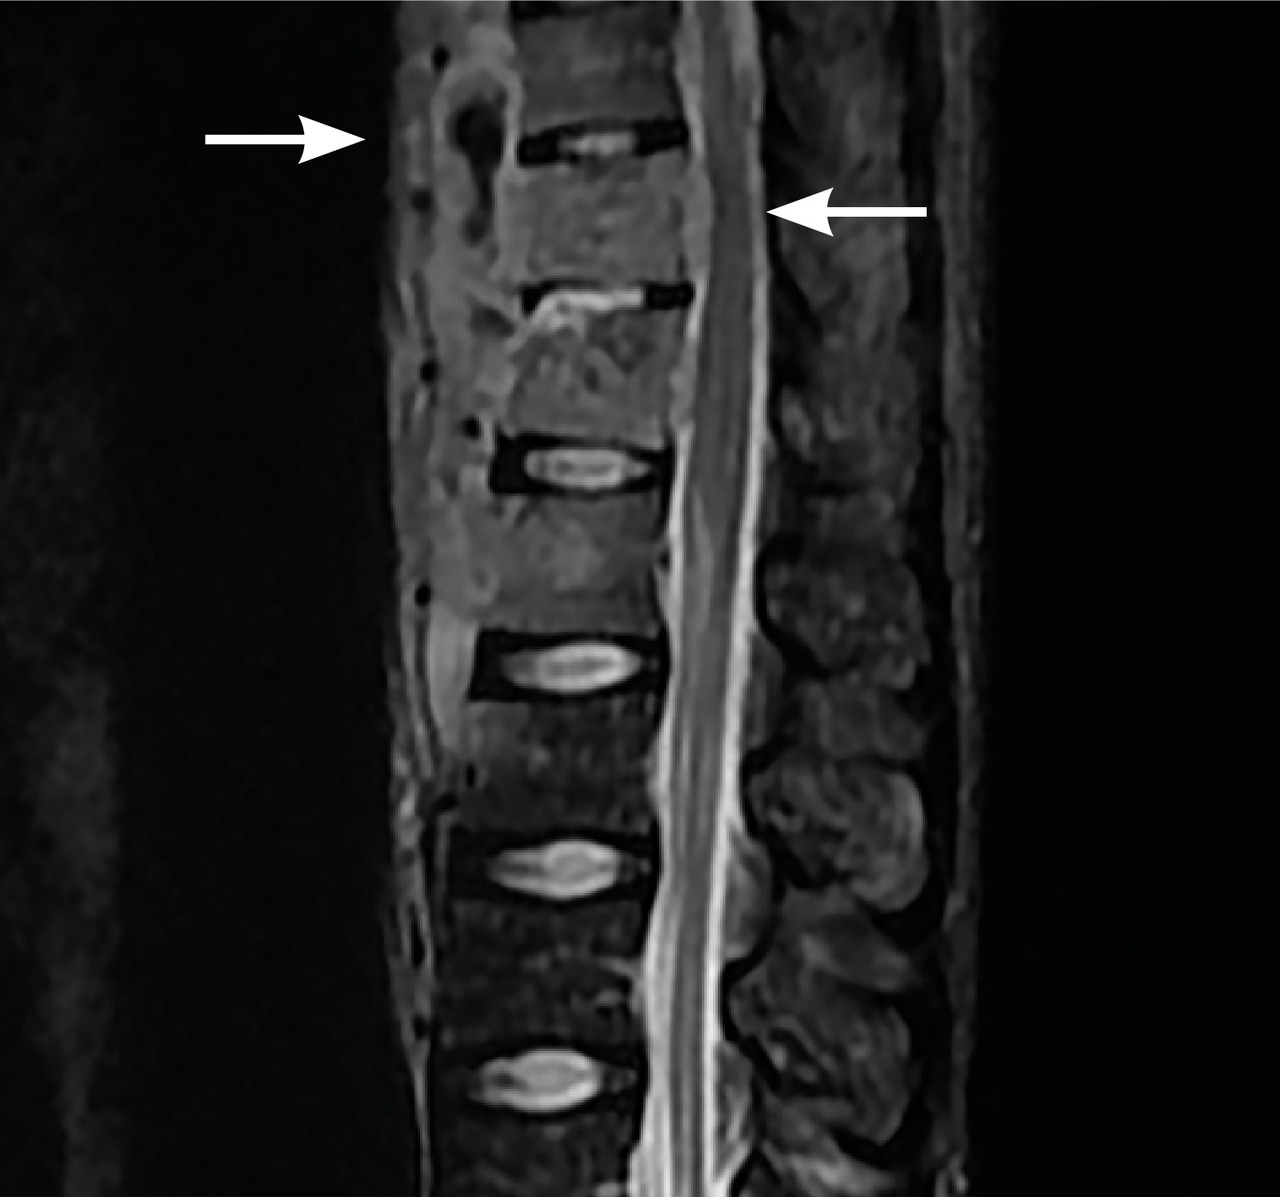

L’imagerie montrait : sur la tomodensitométrie (TDM) thoracique une miliaire tuberculeuse pulmonaire et des adénopathies médiastinales ; sur l’imagerie par résonance magnétique (IRM) du rachis une spondylodiscite T11-T12 (fig. 1 ) ; sur la TDM abdominale des abcès paravertébraux de T9 à T12 le long des psoas (fig. 2 , flèches blanches) et des lésions micronodulaires hépatiques multiples (fig. 2 , flèche jaune) ; sur l’IRM myocardique des signes de péricardite (fig. 3 , flèches). La ponction lombaire montrait une méningite. Un tuberculome était visible sur l’IRM cérébrale, entouré d’un œdème périlésionnel (fig. 4 ). Le diagnostic de tuberculose disséminée était prouvé par polymerase chain reaction sur une ponction d’abcès. Compte tenu de l’atteinte neuroméningée, un traitement adjuvant par corticothérapie s’imposait dans le cas présent, de même qu’une antibiothérapie de 9 à 12 mois.1